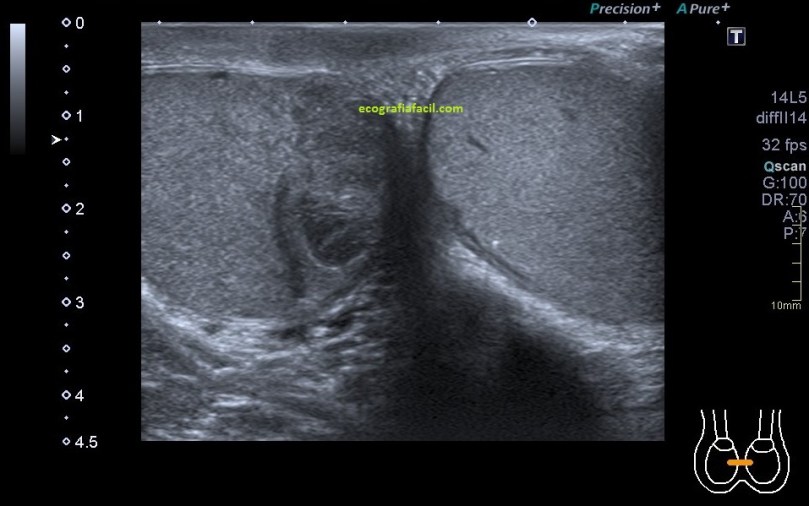

La mayoría de las exploraciones están dentro de la normalidad, este aspecto:

En algunas ocasiones podemos encontrarnos esto:

Compara la imagen 1 y la 2, grábala en tu memoria fotográfica. Ambas son unas imágenes en corte longitudinal del teste derecho de dos pacientes distintos.